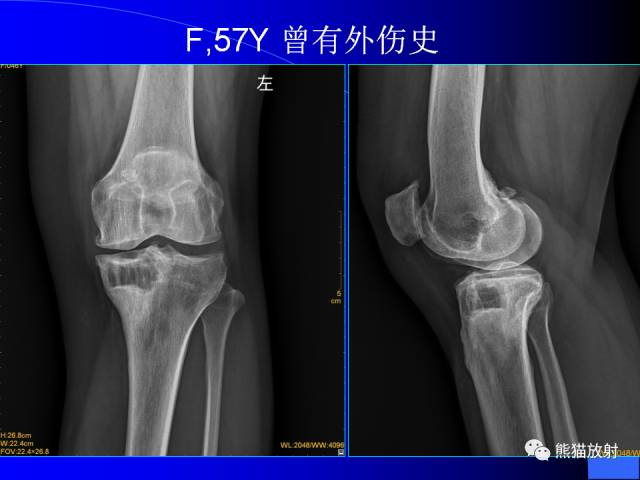

膝关节周围囊肿是较常见的病变,可以是原发的,多见于青年及儿童,囊内容物通常是黏液;也可以是继发的,多与关节腔相通,内含一般黏性的滑液,常继发于膝关节骨关节炎、类风湿关节炎、非特异性滑膜炎、半月板损伤、髌骨软骨软化症等。